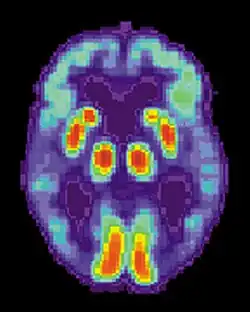

Parkinson's disease

Parkinson's disease is known to affect selective areas in the frontal lobe area of the brain. Current scientific information suggests that the memory performance problems notably shown in patients are controlled by unusual frontostriatal circuits.[70] Parkinson's patients often have difficulty with the sequence-specific knowledge that is needed in the acquisition step of procedural memory.[71] Further evidence suggests that the frontal lobe networks relate to executive function and only act when specific tasks are presented to the patient. This tells us that the frontostriatal circuits are independent but able to work collaboratively with other areas of the brain to help with various things such as paying attention or focusing.[72]

Schizophrenia

MRI studies have shown that schizophrenic patients not currently taking related medication have a smaller putamen, part of the striatum that plays a very important role in procedural memory.[73] Further studies on the brain reveal that schizophrenics have improper basal ganglia communication with the surrounding extrapyramidal system that is known to be closely involved with the motor system and in the coordination of movement.[74] The most recent belief is that functional problems in the striatum of schizophrenic patients are not significant enough to seriously impair procedural learning, however, research shows that the impairment will be significant enough to cause problems improving performance on a task between practice intervals.[75]